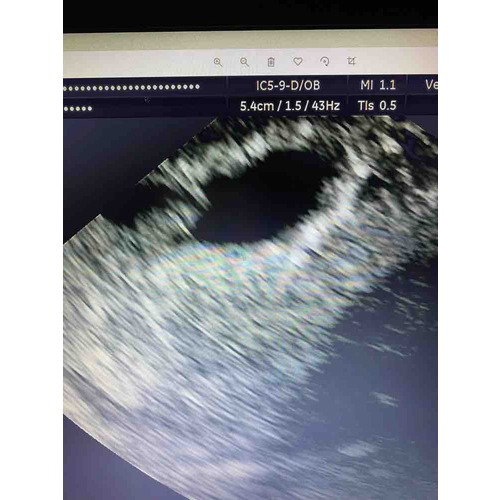

Hoi! Ja ik had een kloppend hartje! Eerst kon ze niks vinden en na 20 min eindelijk gevonden. Ik probeer nu maar zo te denken zo lang ik geen buikpijn/krampen of rood bloedverlies heb zal het wel goedkomen.. want ik maakte mezelf echt helemaal gek . Maar ik zie bij jou ook geen vruchtje zitten ? Hoe heeft ze het opgemeten bij jou?

Oh wat mooi zeg! Ik was binnen 10 minuten al buiten dus misschien is dat het verschil haha! Ja dat is inderdaad een goede gedachte moet ik ook maar eens doen! Nee dat klopt waarschijnlijk omdat ik te vroeg was en er enkel nu alleen een vruchtzakje is hopelijk is er morgen meer.. inwendig is het opgemeten.

Ze zeggen een gemiste miskraam omdat het vruchtzakje niet gegroeid is en het geen ronde vorm had. Ik weet niet wat ik moet geloven.. ze vragen nog geen eens naar mijn cyclus terwijl ik een cyclus van 36 dagen heb? Volgens mij ben ik gewoon nog te vroeg om iets te zien? Wat denken jullie?

Nou ja zeg ! Dit meen je niet ? Heb je een foto ? Hoever dacht je zelf ook alweer te zijn ? Vind dit erg raar allemaal ..